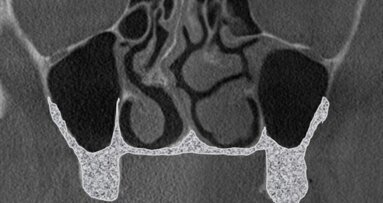

Anatomiczna klasyfikacja została stworzona na podstawie analizy 200 obrazów tomografii wolumetrycznej u pacjentów z całkowitym bezzębiem lub z brakami skrzydłowymi. Każde z tych badań (CBCT) obejmowało 2 zatoki szczękowe: lewą i prawą. Jest to klasyfikacja ułatwiająca podjęcie decyzji, która z metod podnoszenia zatoki szczękowej będzie dla pacjenta odpowiednia i czyli pomaga w doborze metody do przypadku.

Klasyfikację oparto na obrazie z tomografii, jaki uzyskuje się w przekrojach czołowych (wieńcowych) lub prostopadłych do krzywej panoramicznej ułożonej równolegle do łuku zębowego górnego. Klasa „zero” (Tab. 1) została wyróżniona jako sytuacja kliniczna, w której brak bezwzględnych wskazań do zabiegu podniesienia dna zatoki szczękowej z 2 powodów:

Kolejne klasy wyróżnia się na podstawie grubości kostnej ściany przedsionkowej zatoki lub podniebiennej. Jeżeli ściana przedsionkowa jest cieńsza niż podniebienna, wówczas w domyśle łatwiejszy dostęp jest od przedsionka, więc przypadek klasyfikuje się do klasy pierwszej.

Występują jednak sytuacje, kiedy to w badaniu CBCT zauważamy jednakowej grubości ścianę przedsionkową oraz podniebienną. Jest to sytuacja, w której przypadek przyporządkowujemy do klasy drugiej.

W chwili, gdy ściana podniebienna jest cieńsza niż policzkowa, występuje klasa trzecia. U tego samego pacjenta może wystąpić anatomicznie klasa pierwsza po stronie prawej i klasa druga po stronie lewej. Różnice te związane są z takimi czynnikami, jak: